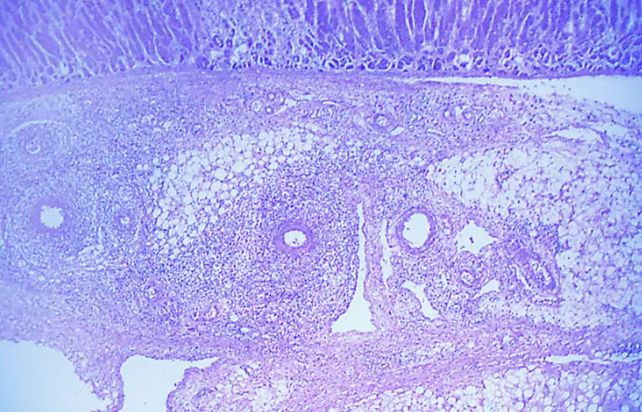

Wegner disease

Affects small vessels in an aggressive way, it is classified as systemic necrotizing granlumatous vasculitis of unknown etiology.

Clinical features include: hematouria and protinurea, usually affects the lungs, similar to goodpasteur syndrome, affects the lungs by pneumonitis